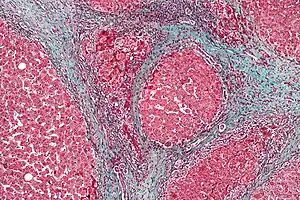

However, cirrhosis is defined by its pathological features on microscopy: (1) the presence of regenerating nodules of hepatocytes and (2) the presence of fibrosis, or the deposition of connective tissue between these nodules. The pattern of fibrosis seen can depend on the underlying insult that led to cirrhosis. Fibrosis can also proliferate even if the underlying process that caused it has resolved or ceased. The fibrosis in cirrhosis can lead to destruction of other normal tissues in the liver: including the sinusoids, the space of Disse, and other vascular structures, which leads to altered resistance to blood flow in the liver, and portal hypertension.[38]

Histopathology of steatohepatitis with established cirrhosis, with thick bands of fibrosis (Van Gieson's stain)[39]_(5690946257).jpg.webp) Trichrome stain, showing cirrhosis as a nodular texture surrounded by fibrosis (wherein collagen is stained blue).

Trichrome stain, showing cirrhosis as a nodular texture surrounded by fibrosis (wherein collagen is stained blue).

As cirrhosis can be caused by many different entities which injure the liver in different ways, cause-specific abnormalities may be seen. For example, in chronic hepatitis B, there is infiltration of the liver parenchyma with lymphocytes.[38] In cardiac cirrhosis there are erythrocytes and a greater amount of fibrosis in the tissue surrounding the hepatic veins.[40] In primary biliary cholangitis, there is fibrosis around the bile duct, the presence of granulomas and pooling of bile.[41] Lastly in alcoholic cirrhosis, there is infiltration of the liver with neutrophils.[38]